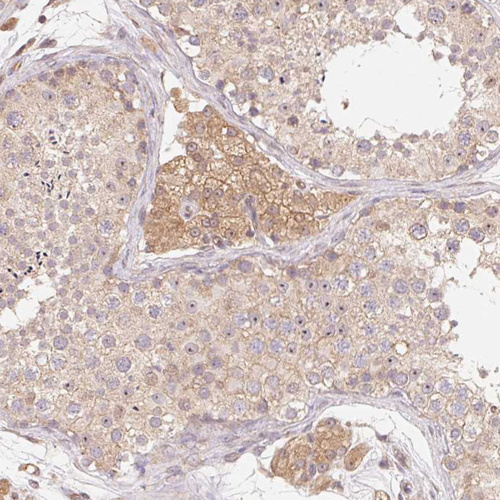

Immunohistochemical staining of human pancreas shows strong cytoplasmic positivity in exocrine glandular cells.